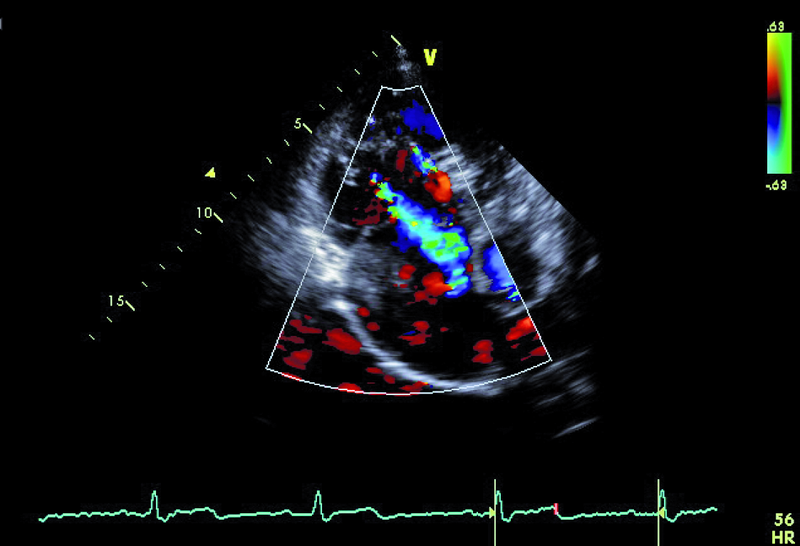

Cechy anomalii Ebsteina łatwo zidentyfikować. Należy zwrócić uwagę na odległość między przyczepem płatka przegrodowego zastawki trójdzielnej a przyczepem przedniego płatka zastawki mitralnej (ryc. 1). Fizjologiczne przesunięcie płatków jest niewielkie i zwykle nie przekracza 5-10 mm. Za kryterium rozpoznania anomalii uważa się wartość 20 mm (w przedstawionym przypadku 50 mm). Przemieszczone płatki są zwykle zmienione organicznie, pogrubiałe, często pociągane przez struny ścięgniste. Płatek przedni jest prawidłowo przyczepiony do pierścienia zastawki trójdzielnej, natomiast jest zwykle powiększony i kształtem może przypominać żagiel (ryc. 1-3). Cechą płatka przedniego w anomalii Ebsteina jest także jego nadmierna ruchomość i liczne perforacje powodujące zwykle więcej niż jedną falę zwrotną (ryc. 4). Zatrializowana część prawej komory znajduje się między przemieszczonymi przyczepami płatków przegrodowego i tylnego, a właściwa jama ma zmniejszoną pojemność. To, czy wada daje objawy, zależy od nasilenia niedomykalności trójdzielnej i od współistniejących anomalii. Niedomykalność trójdzielna u tego pacjenta, mimo dużego przemieszczenia płatka przegrodowego, była mała (ryc. 4). Zarejestrowany metodą doplerowską profil prędkości z jednego ze strumieni niedomykalności wskazywał na niepodwyższone ciśnienie w jamie prawej komory (ryc. 5). Funkcja mięśnia prawej komory określona za pomocą pomiaru przemieszczenia bocznej części pierścienia zastawki trójdzielnej była prawidłowa (ryc. 6). Diagnostykę można na tym etapie zakończyć i uznać, że chory kwalifikuje się do dalszej obserwacji. Badanie przezprzełykowe jest potrzebne u pacjentów, u których nie można ocenić dokładnie morfologii zastawki trójdzielnej. Może też być konieczne w przypadku desaturacji krwi tętniczej i podejrzenia często towarzyszącego anomalii ubytku przegrody międzyprzedsionkowej. Warto zaznaczyć, że ubytek zwykle charakteryzuje się przeciekiem prawo-lewym, na skutek dysfunkcji jam prawego serca i wzrostu ciśnienia w jamie prawego przedsionka. W tym przypadku, wobec braku sinicy, badania przezprzełykowego nie wykonano. Cewnikowanie serca także nie jest konieczne, ponieważ chory ma małą niedomykalność trójdzielną i dobrą wydolność fizyczną, a więc nie kwalifikuje się do leczenia operacyjnego.